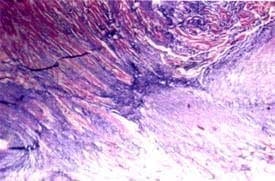

Figura No. 2. Microfotografía el miocardio. Coloración de tricrómico que evidencia zonas fibrosas (azules)

que reemplazan fibras miocárdicas (rojas) 250x.